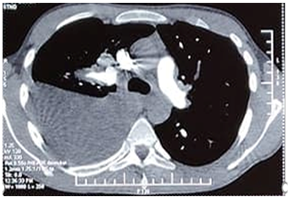

A 21-year-old man was followed for six months in the internal medicine department for Hughes-Stovin syndrome. He presented with pulmonary arterial aneurysms (Figure 1) thrombosis of the hepatic and inferior vena cava veins and recurrent bipolar aphthosis. The patient was treated with colchicine mg per day, oral corticosteroid 60mg per day and monthly boli of cyclophosphamide. The evolution was marked by the occurrence of a state of epilepticus complicated by inhalation pneumopathy due to Staphylococcus Aureus requiring intubation and mechanical ventilation for eight days in intensive care unit. Status epilepticus could not be explained by metabolic, toxic, infectious or iatrogenic causes. There was no concept of trauma and the brain scanner was without abnormalities. Magnetic resonance brain imaging with gadolinium injection showed no parenchymal or vascular lesions. The electroencephalogram showed a non-abnormal pattern. An improvement in the neurological state with no seizure recurrence was obtained under anti-epileptic treatment. The pulmonary examination showed clinical improvement and radiological cleansing. Two weeks later, the patient experienced chest pain with acute dyspnea. The examination found an increase in the sonorityduring percussion of the thorax with a decrease in respiratory sounds in auscultation. Chest X-ray and thoracic computed tomography scan showed the presence of a left medium-sized pneumothorax (Figure 2A), associated with fusiform aneurysmal dilatationof the apical branch of the Lingula (Figure 2B), and posterolateral atelectasis of the left lower lobe containing pneumatocele blebs. The pneumothorax extended rapidly and became bilateral. The patient was transferred to a resuscitation unit undergoing a chest drainage. The course was marked by severe respiratory distress requiring intubation.The patient had died with an unexplained etiology.

A                                                                               B

Figure 2 Left pneumothorax (A) and pulmonary anevrysms (B) at thoracic computed tomography scan.